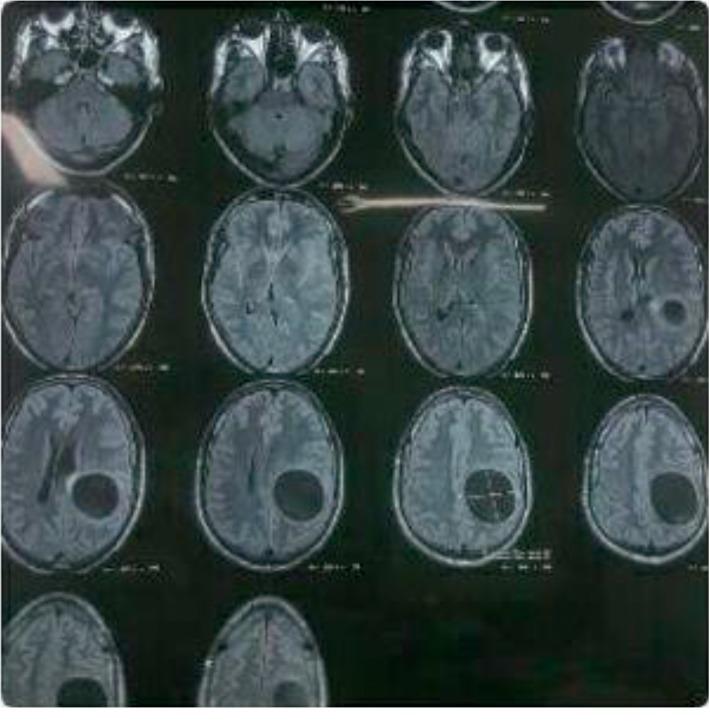

Cystic echinococcosis (CE) is a neglected helminthic disease and major public health problem in several regions of the world. The zoonosis is caused by the larval stage of different cestode species belonging to the genus CE can affect any organ with the liver and lungs being most commonly involved. The brain is involved in less than 2% of the cases. We report a case of a CE1 echinococcal cyst of the brain in an Iranian patient.

囊型包虫病(CE)是一种被忽视的蠕虫病,也是世界上多个地区的主要公共卫生问题。这种人畜共患病由棘球绦虫属不同绦虫物种的幼虫阶段引起。CE可影响任何器官,其中肝脏和肺最常受累。脑部受累的病例不到2%。我们报告了一例伊朗患者脑部CE1型棘球蚴囊肿的病例。